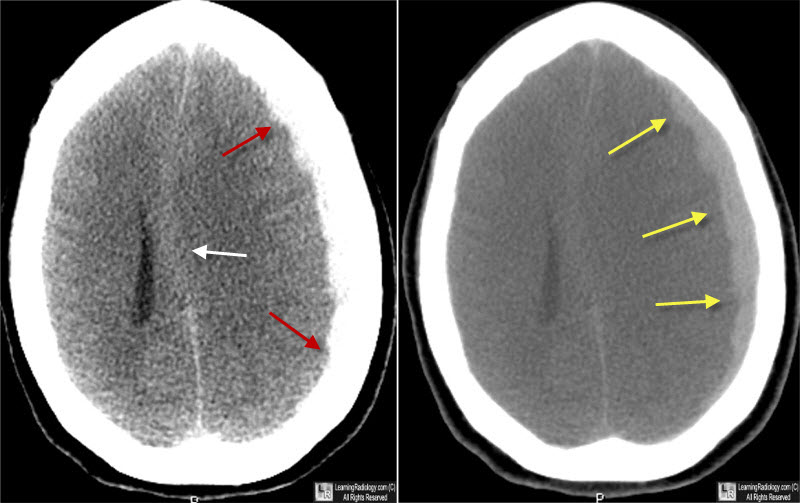

Bypass extra-intracraneal para la obstrucción de las arterias carótida interna o cerebral media

En los pacientes con oclusión sintomática de las arterias carótida interna o cerebral media e insuficiencia hemodinámica, la adición de cirugía de bypass al tratamiento médico no cambió significativamente el riesgo del resultado compuesto de accidente cerebrovascular o muerte dentro de los 30 días o accidente cerebrovascular isquémico ipsilateral más allá de los 30 días a los 2 años.  JAMA, 22 de agosto de 2023.